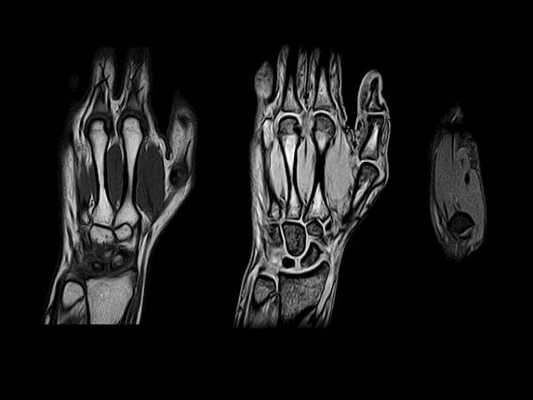

Первая из серии отобранных Т1 МР-томограмм левой кисти в аксиальной проекции. Обратите внимание на локтевые артерию и нерв в канале Гийона, а также на пульсирующий артефакт (двоение) от лучевой артерии на латеральной поверхности тыла запястья: Этот артефакт в некоторых случаях помогает выявить нормальные сосудистые структуры. Аксиальная МР-томограмма левой кисти на уровне крючка крючковидной кости. Обратите внимание, что мышцы тенара начинаются от удерживателя сгибателей. На уровне крючка крючковидной кости локтевая артерия обычно проходит кпереди или с передне-медиальной стороны от крючка, тогда как локтевой нерв и его ветви обычно огибают крючок с латеральной стороны. Первая из серии отобранных Т1 МР-томограмм правой кисти в аксиальной проекции. Обратите внимание на локтевые артерию и нерв в канале Гийона, а также на пульсирующий артефакт (двоение) от лучевой артерии на латеральной поверхности тыла запястья. Этот артефакт в некоторых случаях помогает выявить нормальные сосудистые структуры. Аксиальная МР-томограмма правой кисти на уровне крючка крючковидной кости. Обратите внимание, что мышцы тенара начинаются от удерживателя сгибателей. На уровне крючка крючковидной кости локтевая артерия обычно проходит кпереди или с передне-медиальной стороны от крючка, тогда как локтевой нерв и его ветви обычно огибают крючок с латеральной стороны. Аксиальная Т1 МР-томограмма левой кисти, полученная через основания пястных костей. Длинная ладонная мышца прикрепляется к ладонному апоневрозу (листок фасции кнаружи от удерживателя сгибателей) и имеет вид срединного утолщения ладонного апоневроза. Мышца практически не имеет функционального значения, поэтому ее длинное сухожилие часто используется в качестве трансплантата при восстановлении других сухожилий. Аксиальная Т1 МР-томограмма левой кисти, полученная через середины пястных костей. На этом уровне мы находимся за пределами запястного канала. На срезе начинают появляться червеобразные мышцы, прилежащие к сухожилиям сгибателей. Аксиальная Т1 МР-томограмма правой кисти, полученная через основания пястных костей. Длинная ладонная мышца прикрепляется к ладонному апоневрозу (листок фасции кнаружи отудерживателя сгибателей) и имеет вид срединного утолщения ладонного апоневроза. Мышца практически не имеет функционального значения, поэтому ее длинное сухожилие часто используется в качестве трансплантата при восстановлении других сухожилий. Аксиальная Т1 МР-томограмма правой кисти, полученная через середины пястных костей. На этом уровне мы находимся за пределами запястного канала. На срезе начинают появляться червеобразные мышцы, прилежащие к сухожилиям сгибателей. На аксиальной Т1 МР-томограмме левой кисти показаны дистальные отделы тел пястных костей. Межсухожильные тяжи—это фиброзные пучки, соединяющие между собой сухожилия разгибателей II-V пальцев непосредственно проксимальнее пястно-фаланговых суставов. Эти фиброзные пучки предотвращают латеральное смещение сухожилий разгибателей над пястными костями. Вследствие наличия этих соединений, разгибание пальцев может оставаться относительно сохранным при полном разрыве одного из сухожилий общего разгибателя пальцев проксимальнее тяжа, и такое повреждение может не проявляться клинически. На аксиальной Т1 МР-томограмме левой кисти можно увидеть головку V пястной кости и дистальные отделы II-IV пястных костей. На аксиальной Т1 МР-томограмме правой кисти показаны дистальные отделы тел пястных костей. Межсухожильные тяжи—это фиброзные пучки, соединяющие между собой сухожилия разгибателей II-V пальцев непосредственно проксимальнее пястно-фаланговых суставов. Эти фиброзные пучки предотвращают латеральное смещение сухожилий разгибателей над пястными костями. Вследствие наличия этих соединений, разгибание пальцев может оставаться относительно сохранным при полном разрыве одного из сухожилий общего разгибателя пальцев проксимальнее тяжа, и такое повреждение может не проявляться клинически. На аксиальной Т1 МР-томограмме правой кисти можно увидеть головку V пястной кости и дистальные отделы II-IV пястных костей. На аксиальной Т1 МР-томограмме левой кисти все еще остаются видны головки II-IV пястных костей. Латеральные вырезки головок пястных костей служат местами начала коллатеральных связок, которые имеют сигнал промежуточной интенсивности и лежат под сагиттальными и латеральными пучками. Глубокие поперечные связки запястья соединяют ладонные пластинки II-V пальцев. На аксиальной Т1 МР-томограмме левой кисти показаны проксимальные фаланги. Латеральные пучки выявляются в виде латеральных утолщений сухожильного растяжения, а сухожилие общего разгибателя пальцев выглядит как центральное утолщение сухожильного растяжения. Поскольку срез получен проксимальнее проксимальных межфаланговых суставов, мы понимаем, что все еще находимся на уровне латеральных пучков, а не соединенных сухожилий. На аксиальной Т1 МР-томограмме правой кисти все еще остаются видны головки II-IV пястных костей. Латеральные вырезки головок пястных костей служат местами начала коллатеральных связок, которые имеют сигнал промежуточной интенсивности и лежат под сагиттальными и латеральными пучками. Глубокие поперечные связки запястья соединяют ладонные пластинки II-V пальцев. На аксиальной Т1 МР-томограмме правой кисти показаны проксимальные фаланги. Латеральные пучки выявляются в виде латеральных утолщений сухожильного растяжения, а сухожилие общего разгибателя пальцев выглядит как центральное утолщение сухожильного растяжения. Поскольку срез получен проксимальнее проксимальных межфаланговых суставов, мы понимаем, что все еще находимся на уровне латеральных пучков, а не соединенных сухожилий.